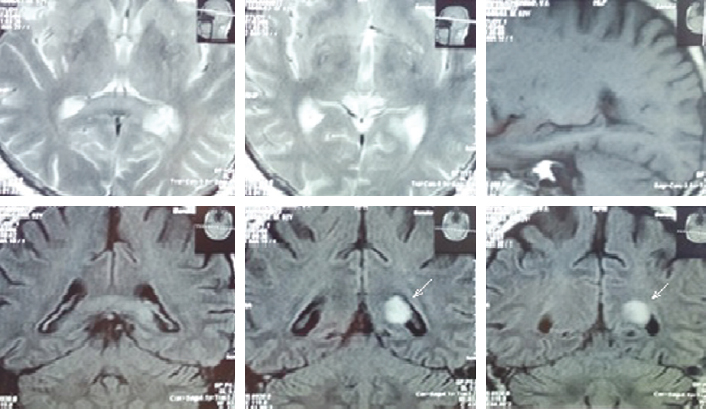

В марте 2006 г. внезапно появились нарушения чувствительности в правой половине лица, тела и конечностей; ухудшение зрения на правый глаз (диагноз офтальмолога: эрозия роговицы, снижение остроты зрения на правый глаз). При магнитно-резонансной томографии (МРТ) данных за острое нарушение мозгового кровообращения (ОНМК) получено не было, однако выявлено глиальное образование размерами 2,3 × 1,5 × 0,8 мм в проекции щипцов мозолистого тела и заднего рога левого бокового желудочка (рис. 1).

Рис. 1. МРТ головного мозга. Выявлено глиальное образование размерами 2,3 × 1,5 × 0,8 мм в проекции щипцов мозолистого тела и заднего рога левого бокового желудочка

В марте 2016 г. появились жалобы на онемение в левой стопе. Выполнена МРТ головного мозга, при которой паравентрикулярно в правой лобной доле выявлен участок кистозно-глиозных изменений диаметром 30 мм. МР-картина последствий ОНМК в бассейне правой среднемозговой артерии, дисциркуляторной энцефалопатии, расширение субарахноидального пространства.